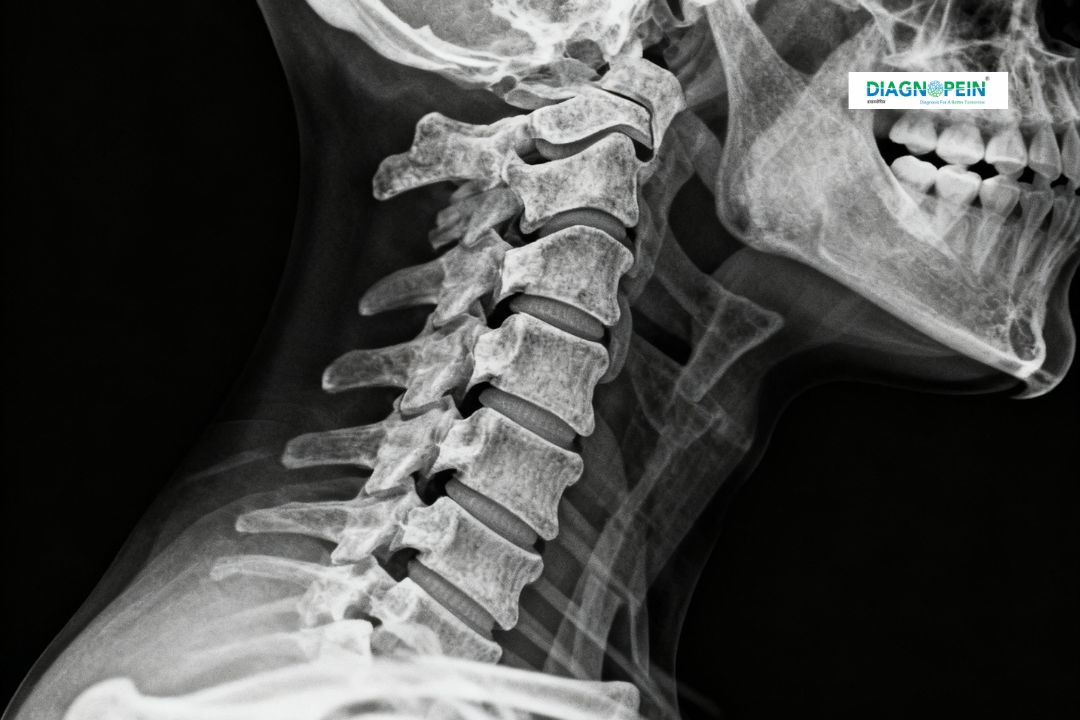

An X-Ray Cervical Spine Lateral View is a quick and effective diagnostic imaging test that captures detailed side-view images of the neck or cervical spine. It helps doctors evaluate the alignment, structure, and health of the vertebrae and surrounding tissues. At Diagnopein in karad, this imaging test is performed using the latest digital X-ray technology to ensure precise visualization of bones and joints for accurate diagnosis.

This test is commonly recommended for patients experiencing neck pain, stiffness, numbness, or injury. It provides valuable insights into possible fractures, dislocations, arthritis, infections, or other spinal abnormalities, allowing early and effective treatment.

The lateral view provides a clear, detailed side image that helps physicians understand the structural integrity of the neck bones. Because this technique covers the entire cervical spine in one image, it becomes easier to identify even minor shifts or abnormalities.

1. Alignment of cervical vertebrae (C1–C7)

2. Spinal curvature and posture abnormalities

3. Joint spaces and disc height

4. Bone density and presence of lesions

5. Fractures, subluxations, or soft tissue swelling

Through these parameters, the X-Ray Cervical Spine Lateral View at Diagnopein karad helps specialists diagnose a wide range of neck and back conditions effectively.